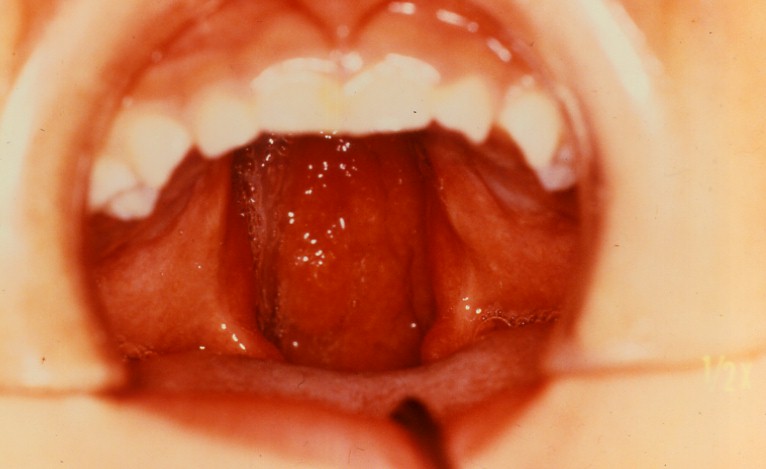

(2)口蓋裂

@口蓋裂とは

口蓋部における破裂があるものを口蓋裂といます。

A分類

軟口蓋、切歯孔までの硬口蓋と軟口蓋、片側性歯槽突起部、両側性歯槽突起部の4型に大きく分けられる。

C症状

口蓋裂では口腔と鼻腔とが交通しているため鼻咽腔が食物で汚染され、二次的に扁桃炎や中耳炎をおこし

やすくなります